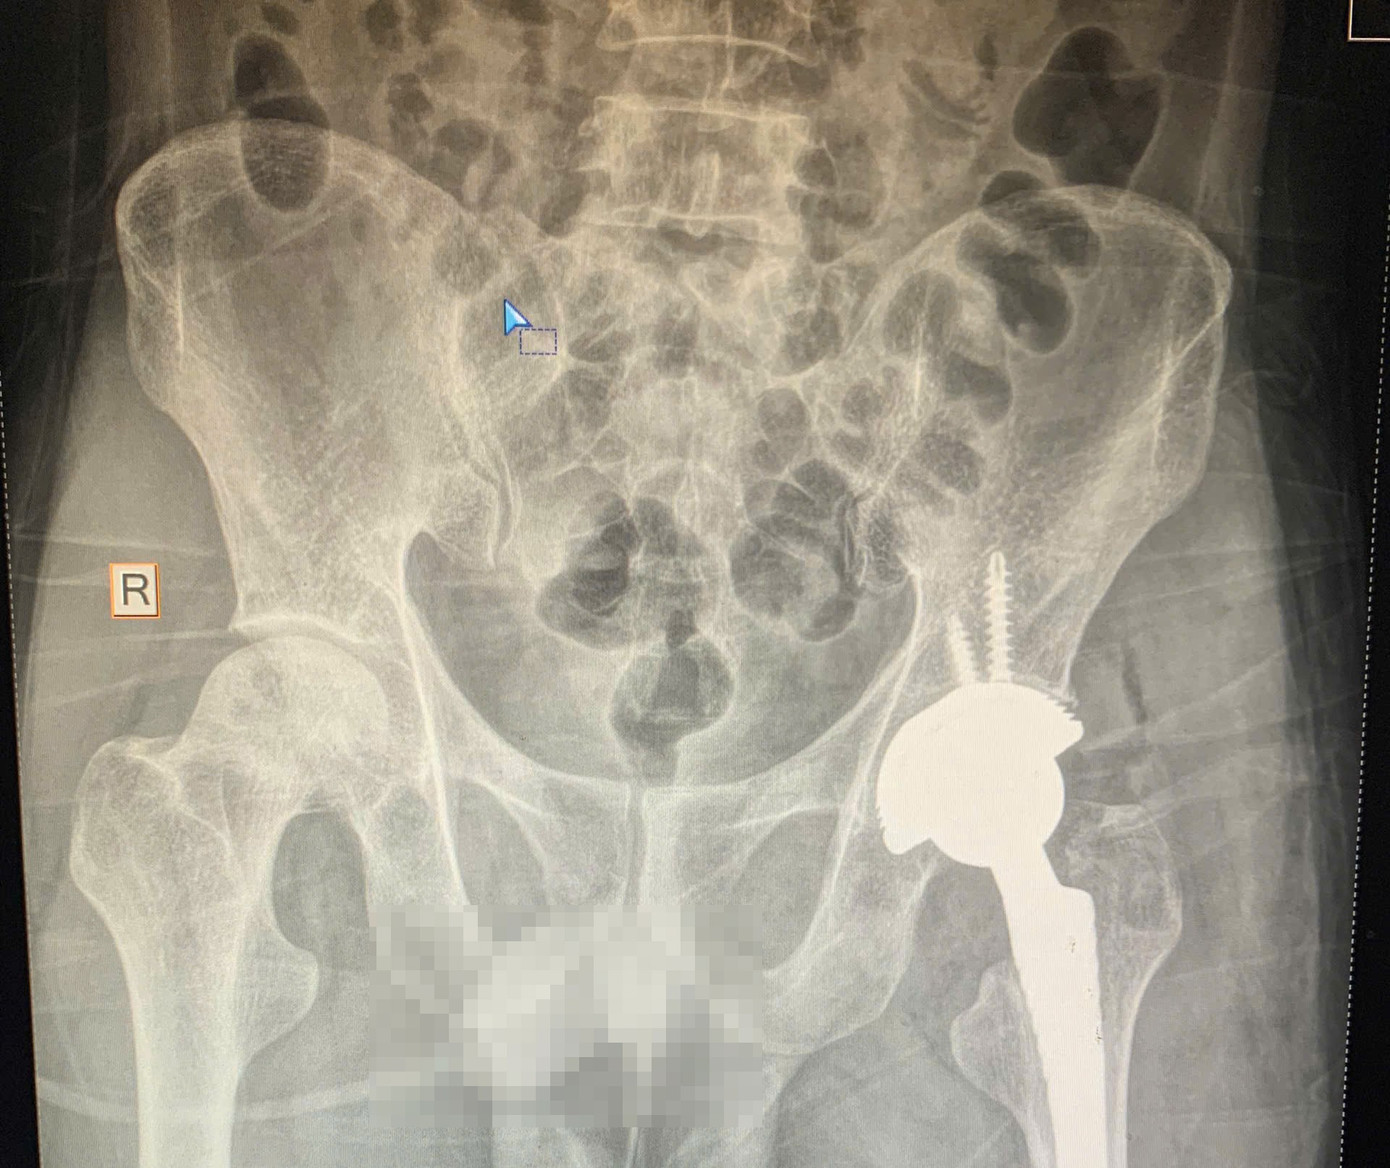

Sau khi thăm khám lâm sàng kết hợp chụp X-quang, bác sĩ xác định chỏm xương đùi trái của bệnh nhân đã bị hoại tử nặng, không còn khả năng bảo tồn. Ê-kíp đã chỉ định phẫu thuật thay khớp háng toàn phần nhằm phục hồi chức năng vận động cho người bệnh.

Trong trường hợp bệnh nhân 36 tuổi nói trên, do phát hiện muộn nên phương án tối ưu là thay khớp háng toàn phần. “Đây là phẫu thuật thay thế khớp háng bị tổn thương bằng khớp nhân tạo, giúp giảm đau hiệu quả, phục hồi khả năng vận động và cải thiện chất lượng cuộc sống cho người bệnh” - BS Thắng chia sẻ.

Ca phẫu thuật được thực hiện thành công sau hơn 1,5 giờ với sự phối hợp của ê kíp Chấn thương Chỉnh hình và Gây mê Hồi sức. Sau mổ, bệnh nhân được theo dõi, chăm sóc và tập phục hồi chức năng theo đúng phác đồ. Hiện tại, người bệnh đã có thể đi lại với khung hỗ trợ, vận động nhẹ nhàng và không còn cảm giác đau như trước.